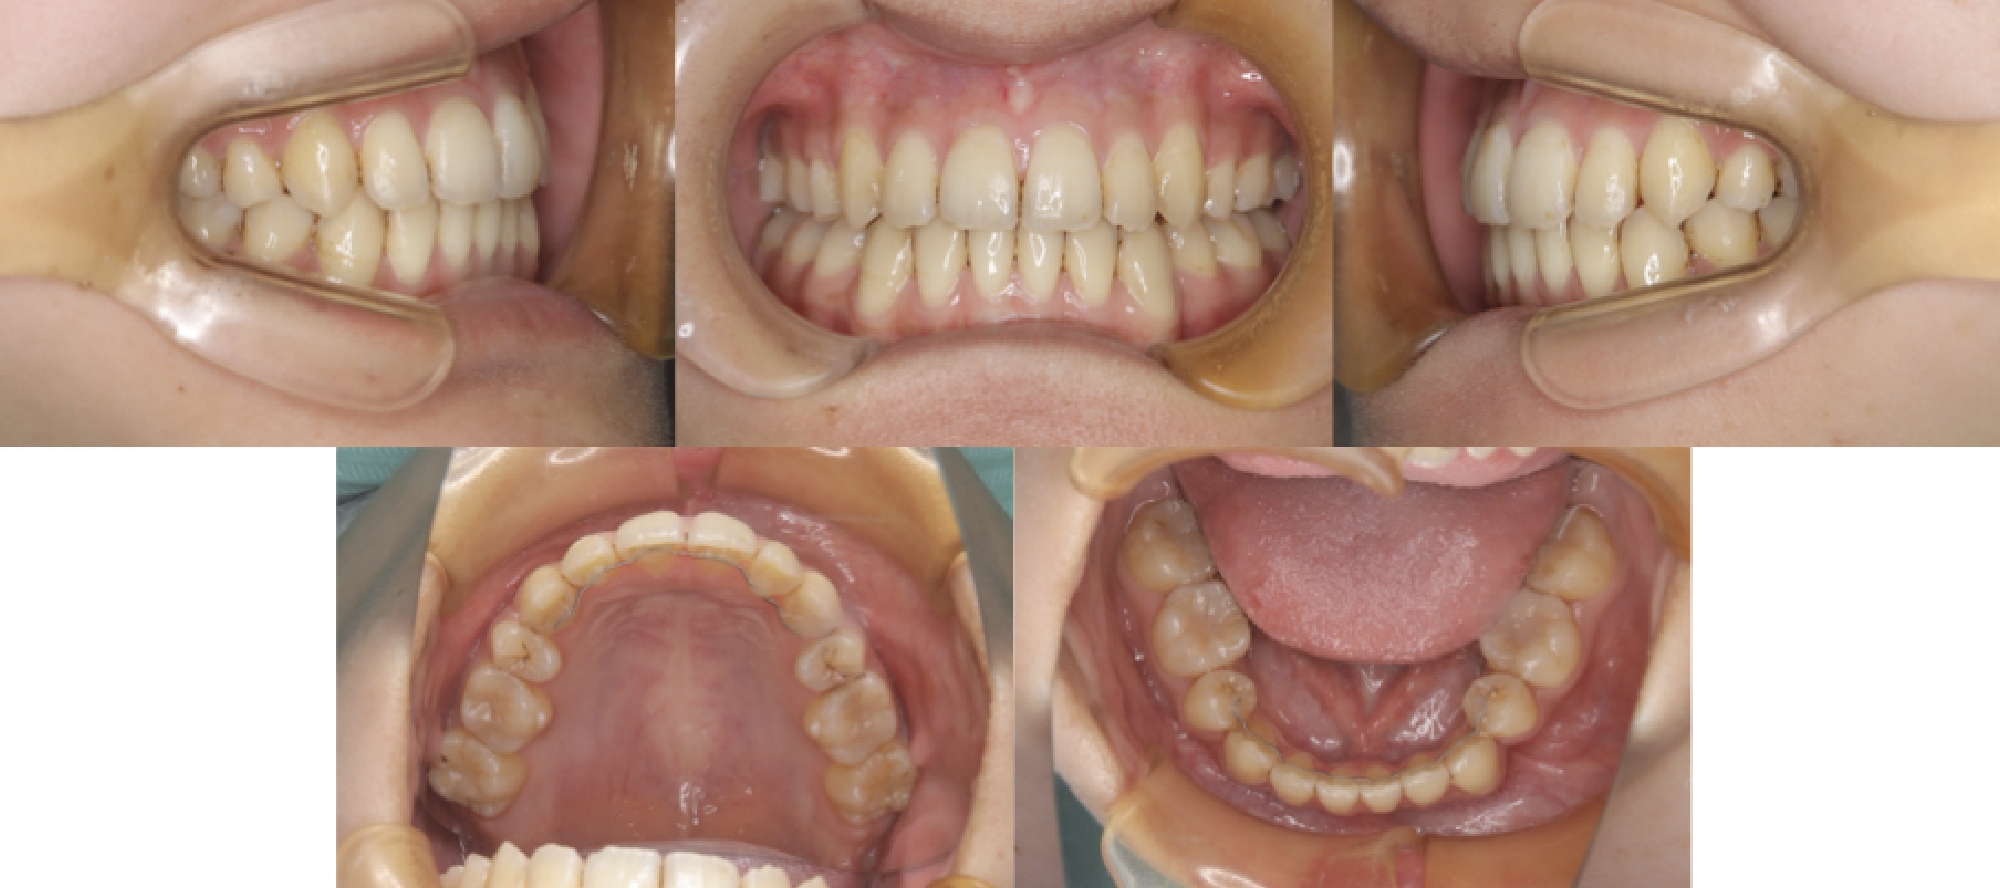

初診時口腔内写真

初診とセットアップ重ね合わせ

治療中

治療終了時

セットアップと終了時重ね合わせ

治療が終わる頃の歯の位置は、事前に作成した3Dセットアップで想定した「骨の中で無理のない位置」とほぼ一致しています。※症例により個人差があります。